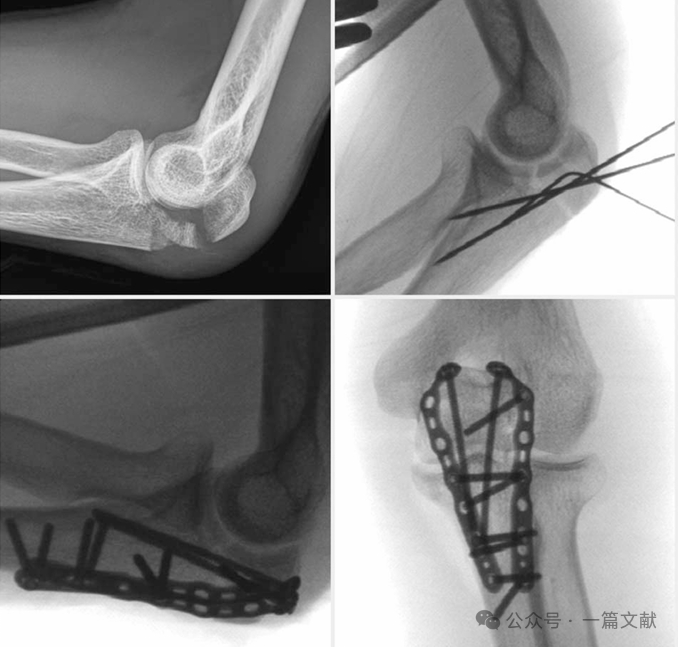

如下图:45岁女性患者,肱骨远端骨折(AO 13C3型): 采用双锁定钢板固定,钢板呈90°放置。鹰嘴截骨术后通过钢丝张力带固定截骨部位。

下图:26岁女性铁人三项运动员,鹰嘴骨折Mayo 2b型:左上图:术前显示鹰嘴骨折。右上图:术中首先对关节面进行复位,并使用克氏针暂时固定。下图:随后采用双钢板固定骨折。